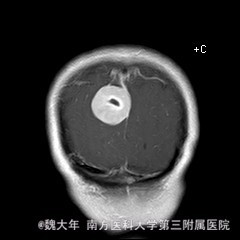

52岁,女性,因“反复头痛10余年,加重1年”入院。患者10余年前无明显诱因始出现头痛,表现为全头发作性胀痛,反复发作,无伴头晕、恶心,无呕吐、肢体抽搐,自行服药(具体不详)及休息后缓解,未予特殊处理。1年前患者觉头痛逐渐加重,以右顶部为甚,劳累或日晒后加重,无头晕、视物旋转,无恶心、呕吐,无发热、寒战,休息或平躺后症状稍有缓解,自行服药不能改善,至当地医院就诊,查颅脑MRI和CT提示“右侧顶部脑膜瘤”。

行“右顶开颅右顶部矢状窦旁脑膜瘤切除术”。取右顶马蹄形手术切口 ,颞侧翻开皮瓣,电刀切开骨膜,中线矢状缝上前、后极各钻一孔,颞侧后方钻一孔,铣刀铣一长方形(7*6cm)骨瓣,见硬膜表面较多点状渗血,予充分止血,悬吊硬膜。 显微镜下切除肿瘤:沿肿瘤边缘剪开硬膜后,见一大小约5*5*6cm肿瘤,沿硬膜内侧面呈匍匐状生长,边界与脑组织有蛛网膜分隔,质地较韧,基底与矢状窦关系密切,靠内侧与大脑镰粘连紧密,血供丰富。仔细分离肿瘤与脑组织的粘连,全切除肿瘤。肿瘤基底与矢窦粘连紧密,并破坏矢状窦侧壁,予低功率电刀反复烧灼,直至肿瘤无明显血供表现。严密止血后常规关颅。

术后1周复查头颅MR未见明显肿瘤残留,拆线后出院。